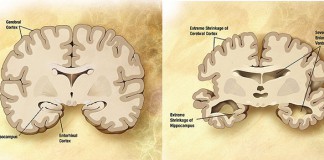

Великие научные открытия XX века, топ 25